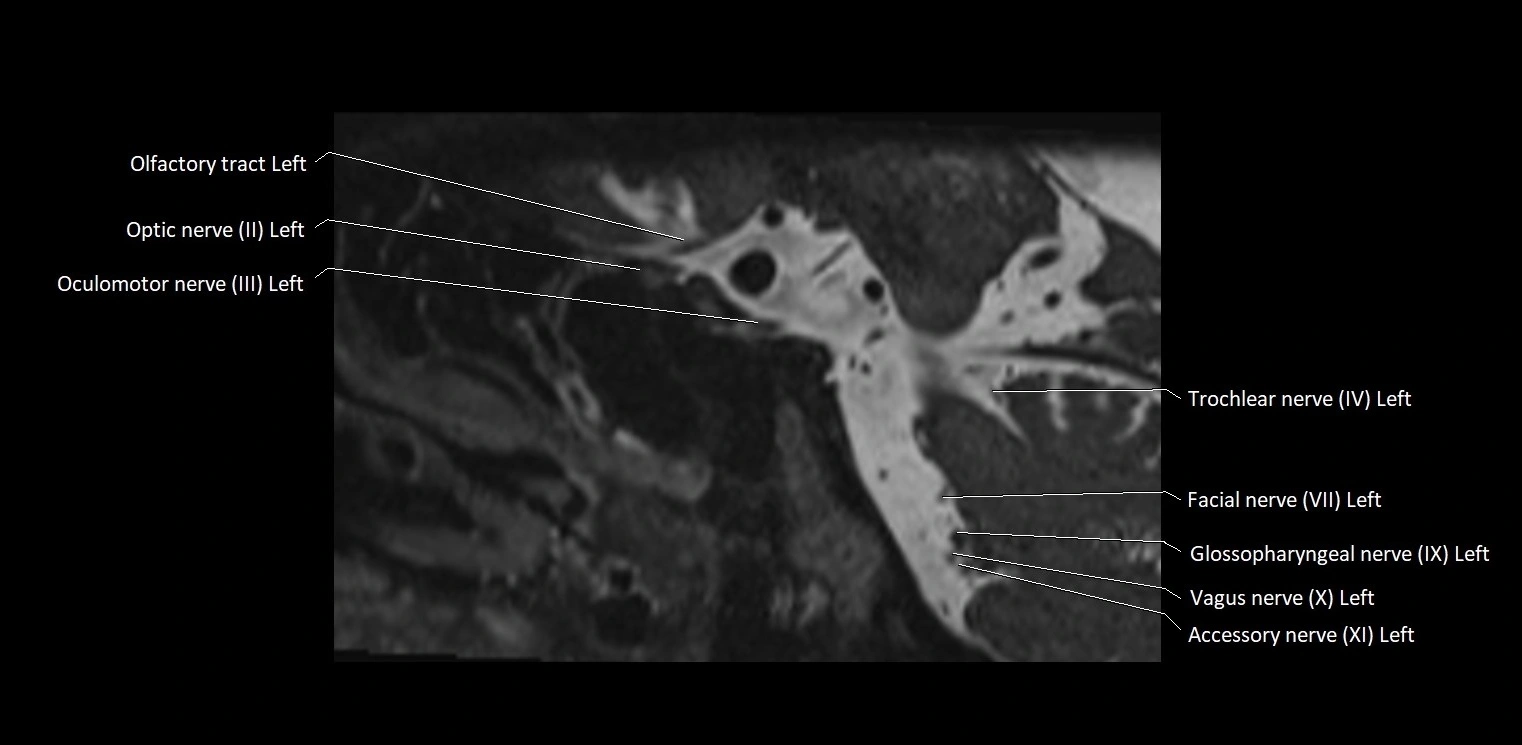

MRI Appearance

• The abducens nerve is a small, thin, linear structure

• Best visualized on high-resolution T2-weighted 3D MRI sequences (e.g., FIESTA or CISS)

• Seen as a hypointense (dark) line running from the brainstem at the pontomedullary junction, traversing the prepontine cistern, and entering Dorello’s canal under the petrosphenoidal ligament, then into the cavernous sinus, and finally the orbit

• May be challenging to visualize in standard MRI due to its small size

• Pathology may be inferred by absence, displacement, or enhancement of the nerve